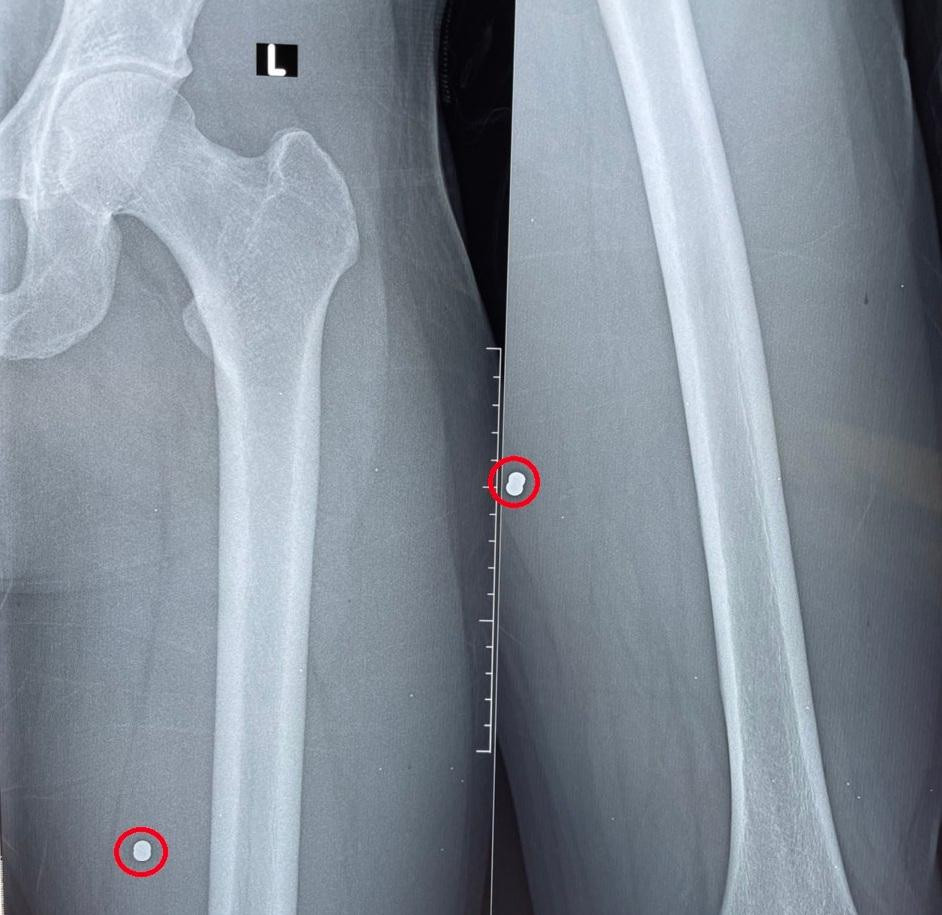

H. nhập viện trong tình trạng vết thương vùng bìu bên trái 1cm, vết thương hở mặt trước đùi trái 0.5cm đang chảy máu, mạch bẹn bên trái bắt rõ.

| Hình ảnh đầu đạn trên phim Xquang. |

Các bác sĩ tiến hành sơ cứu kiểm tra vết thương, xử trí cấp cứu và nghi ngờ dị vật là viên đạn. X-Quang xương đùi trái ghi nhận dị vật cản quang nghi đầu đạn bằng kim loại trong mô mềm vị trí 1/3 trên đùi trái.